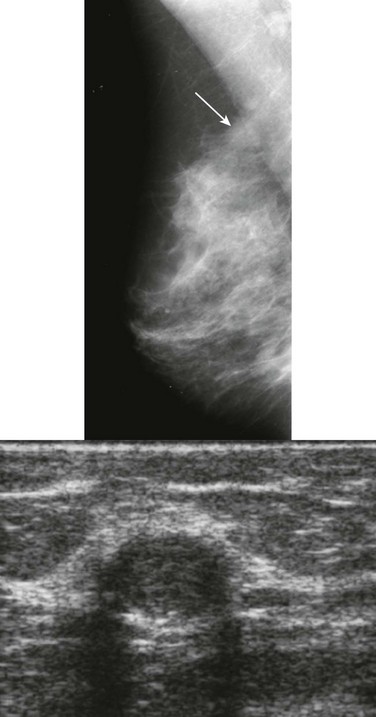

How would a web of tumor cells look on a mammogram or ultrasonography (US)? The mammogram may show only very subtle findings or be completely normal, even in the setting of extensive ILC (Fig. 11-2). Only the densest part of the tumor will be visible on mammography. ILC may appear as a mass with ill-defined or spiculated margins or as architectural distortion with or without a central mass. When a central mass is present, then it is considered a spiculated mass. When there is architectural distortion without a central mass, these lesions are often called the “dark star.” Calcifications are uncommon, though ILC can have associated DCIS. ILC is often seen in only one view, most commonly the craniocaudal (CC) view. This makes sense because the CC view has better compression of the breast tissue than does the mediolateral oblique (MLO) view. Greater compression can bring out the subtle distortion to better advantage. The extent of disease of ILC is not easily assessed on mammography because the edges of that web are not well defined.

FIGURE 11-2 ILC.

A 49-year-old woman with a firm palpable lump in the right breast. Mammogram is normal in the palpable area that is marked by a triangle. US shows multiple hypoechoic areas with shadowing but no discrete mass, which is characteristic of ILC. (Reprinted with permission from Harvey JA. Unusual breast cancers: Useful clues to expanding the differential diagnosis. Radiology 2007;242:683-694.)

On US, ILC may present as a defined mass (see Fig. 11-3) but more often presents as ill-defined areas of shadowing without a distinct mass (see Fig. 11-2). The lines and arcs of tumor can produce bands of shadowing, like the edges of a spider web. Although tumor size is often underestimated by US, this modality is more accurate than clinical examination or mammography in assessing extent of disease.